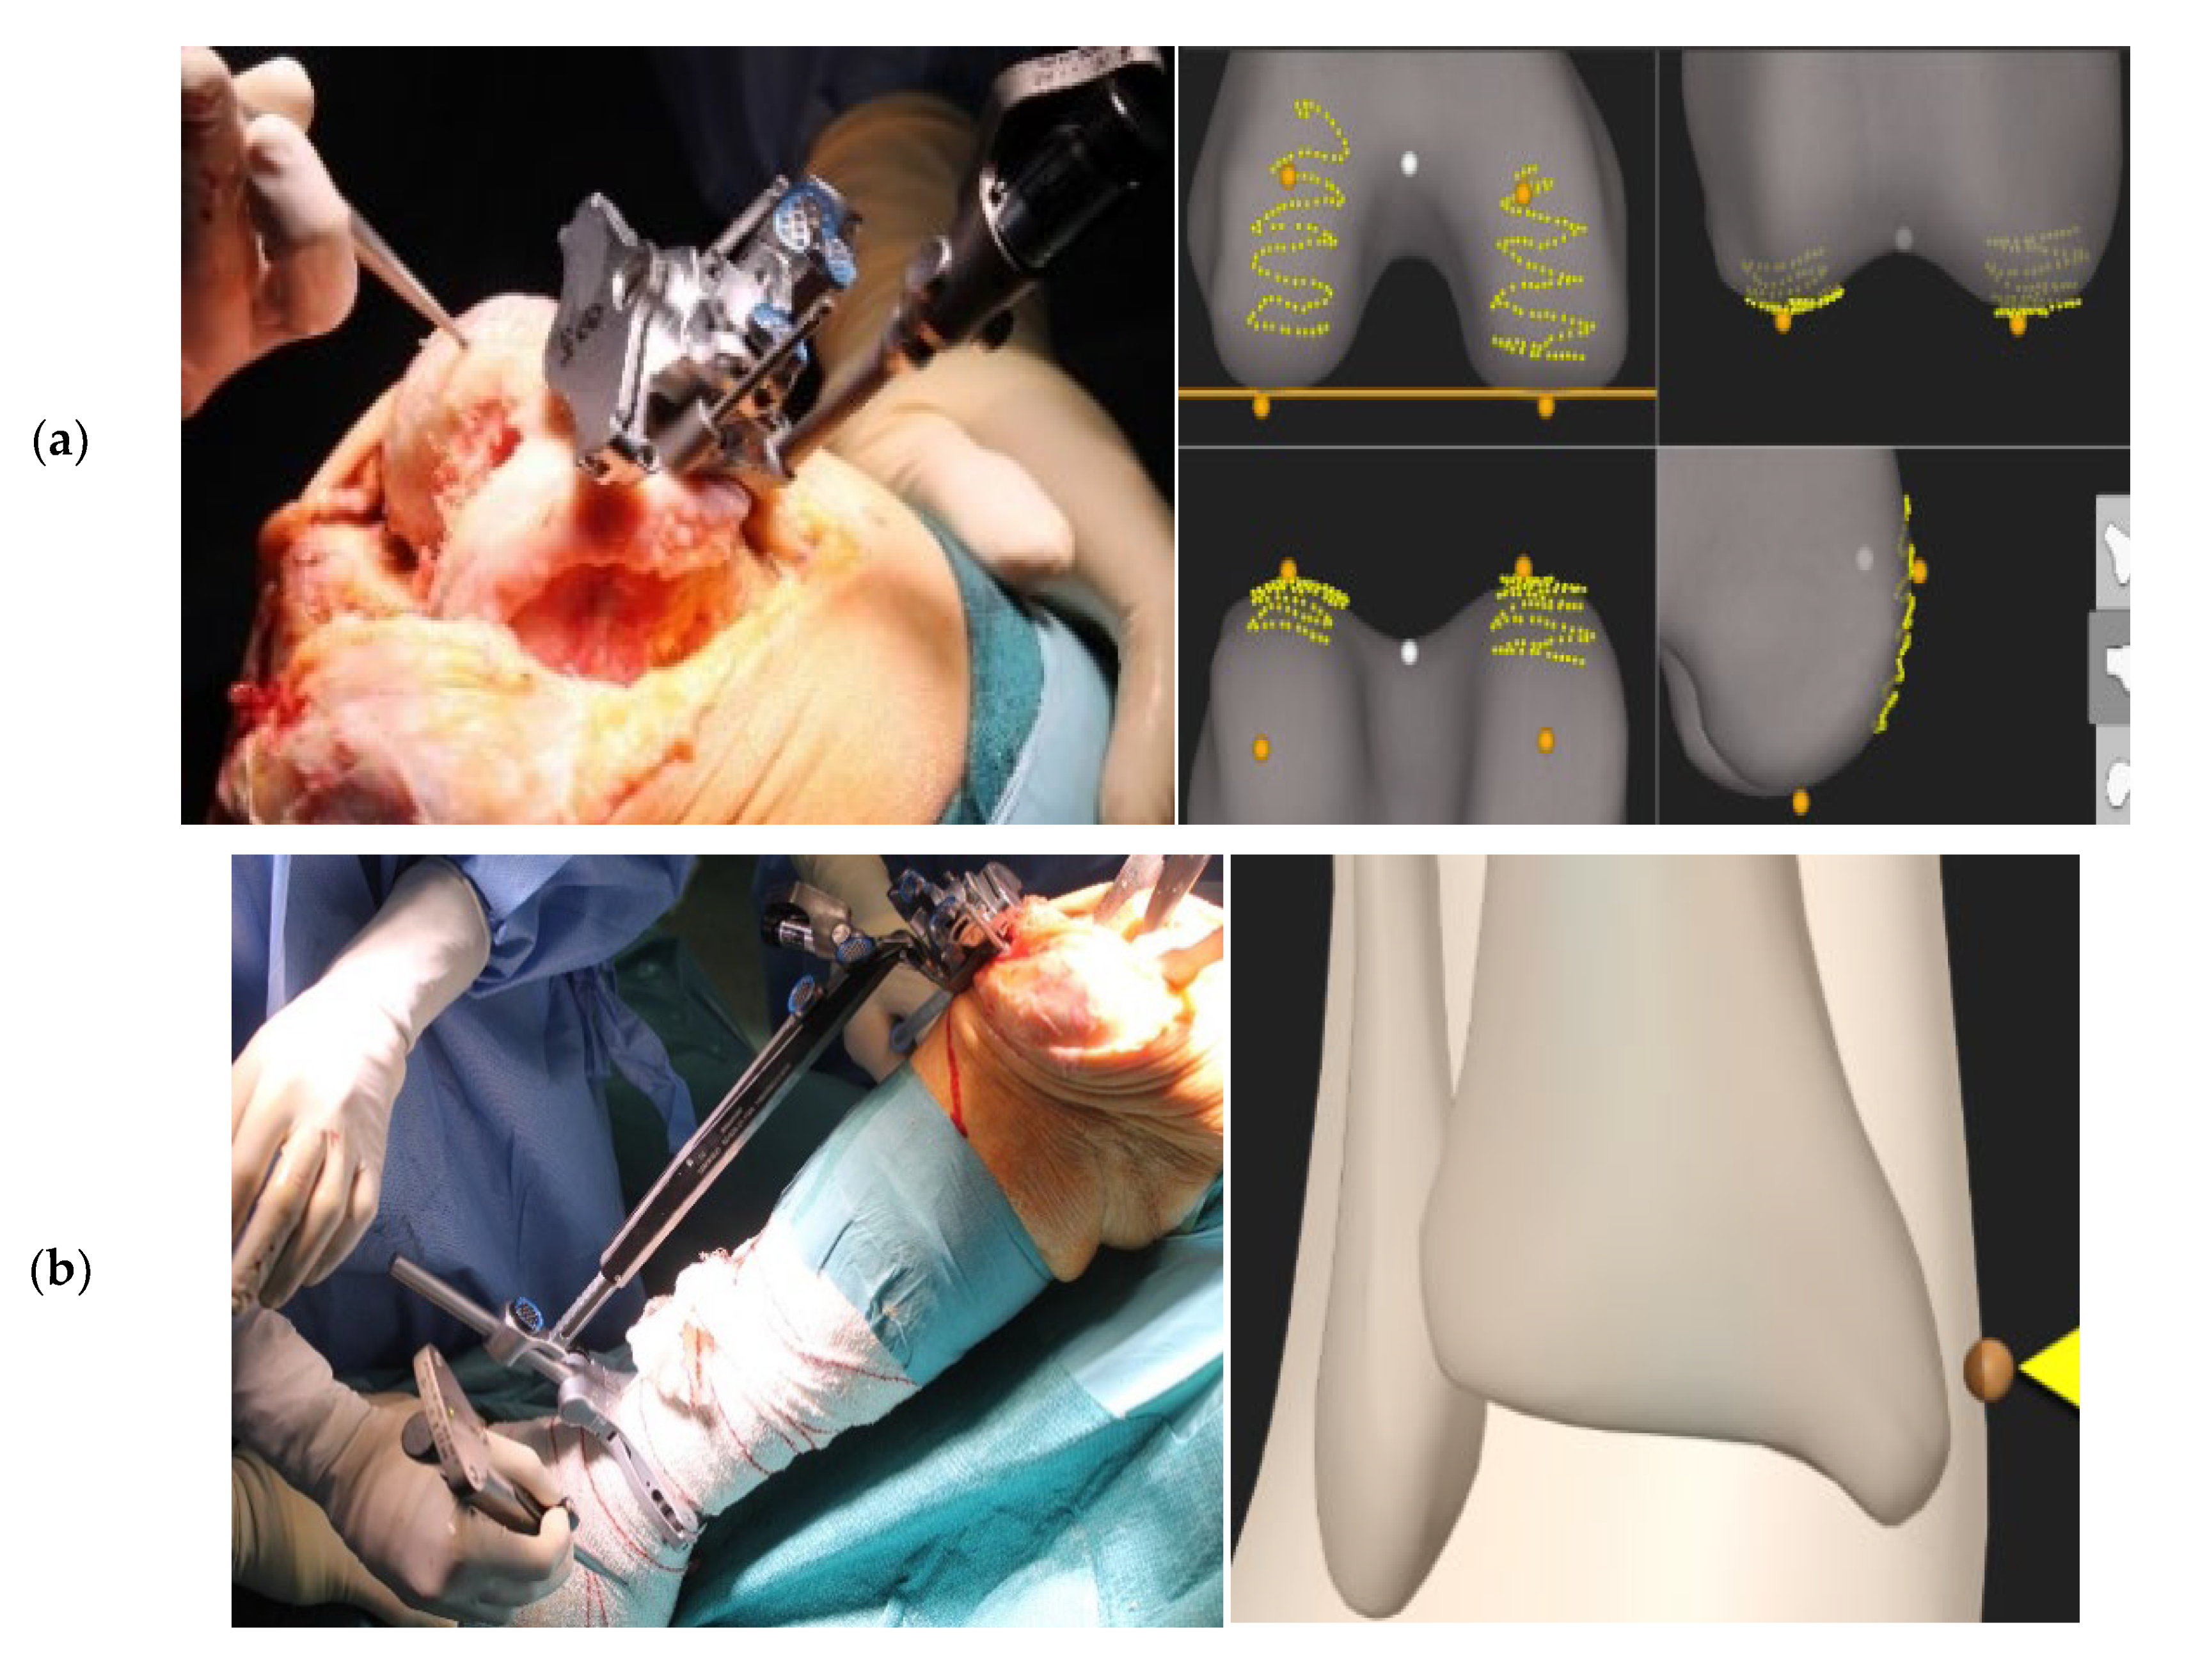

2.2. Surgical Technique